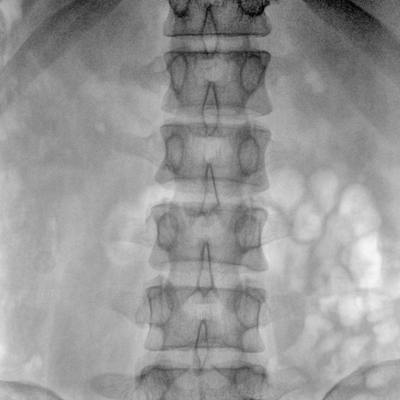

動態(tài)板C形臂 開啟清晰影像新篇章

臨床適用科室:骨科、普通外科、矯形外科、創(chuàng)傷外科、泌尿外科、脊柱外科、疼痛外科、消化科、婦科等科室。

大尺寸動態(tài)平板探測器,高DQE、低噪聲、圖像清晰。采用多分辨率圖像增強(qiáng)處理技術(shù),不同部位不同圖像處理算法,滿足客戶多樣化的需求。

采用智能變頻脈沖透視技術(shù),優(yōu)化圖像質(zhì)量的同時降低輻射劑量,呵護(hù)醫(yī)患健康